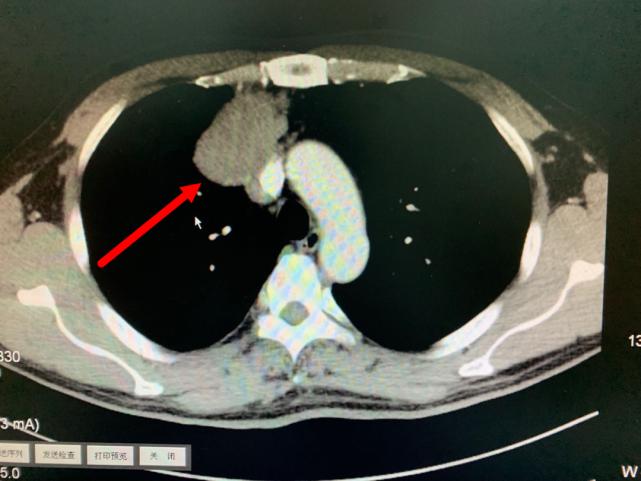

肿瘤与周围血管存在黏连

叶中瑞主任医师通过进一步增强CT检查发现,老方体内的肿瘤巨大、与相邻的重要脏器粘连,界限不清,手术难度较大,且微创手术不适合,于是采取正中劈开胸骨的手术方式。手术过程顺利,术后恢复良好。第二天即下床活动。术后病理结果显示:纵膈肿瘤性质为中度恶性的胸腺肿瘤,后续还需要做进一步的放射治疗,以防止复发。老方在庆辛之余,他告诉叶中瑞主任医师,自己从今年开始每年都按时做体检,争取做到疾病早发现、早治疗,避免错过疾病的最佳治疗时机。

今年11月份,老方因“肠炎”在浙江省立同德医院肛肠科住院。“新冠”期间住院需要常规做胸部CT筛查,检查出来的结果却让他和医生们大吃一惊,胸部CT显示:胸腔内存在一个巨大肿瘤即纵膈肿瘤,大小约10.0cm×6.5cm×7.0cm,大小和一个成人男性拳头差不多。肿瘤紧靠着肺部、心脏及大血管,且与部分大血管有粘连,对重要的脏器已经造成了挤压。在确定胃肠道没有严重病患后,老方被转入心胸外科进一步作检查、治疗。